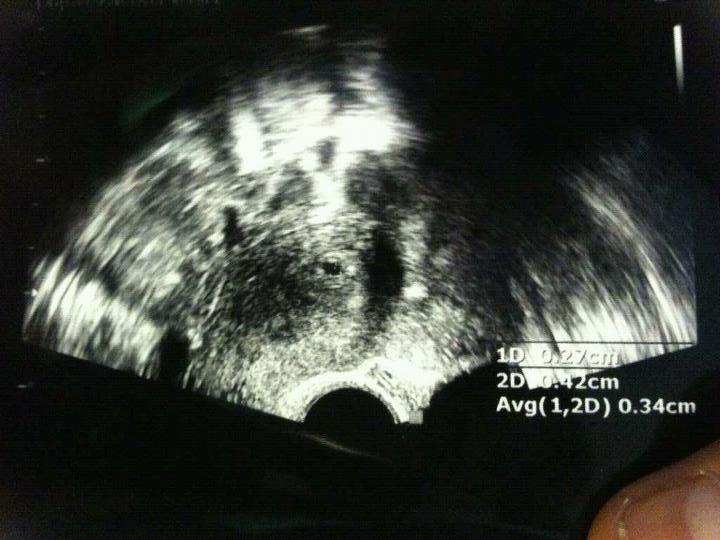

ÀÛÀº Á¡Çϳª·Î ½ÃÀÛÇÑ »ý¸í...